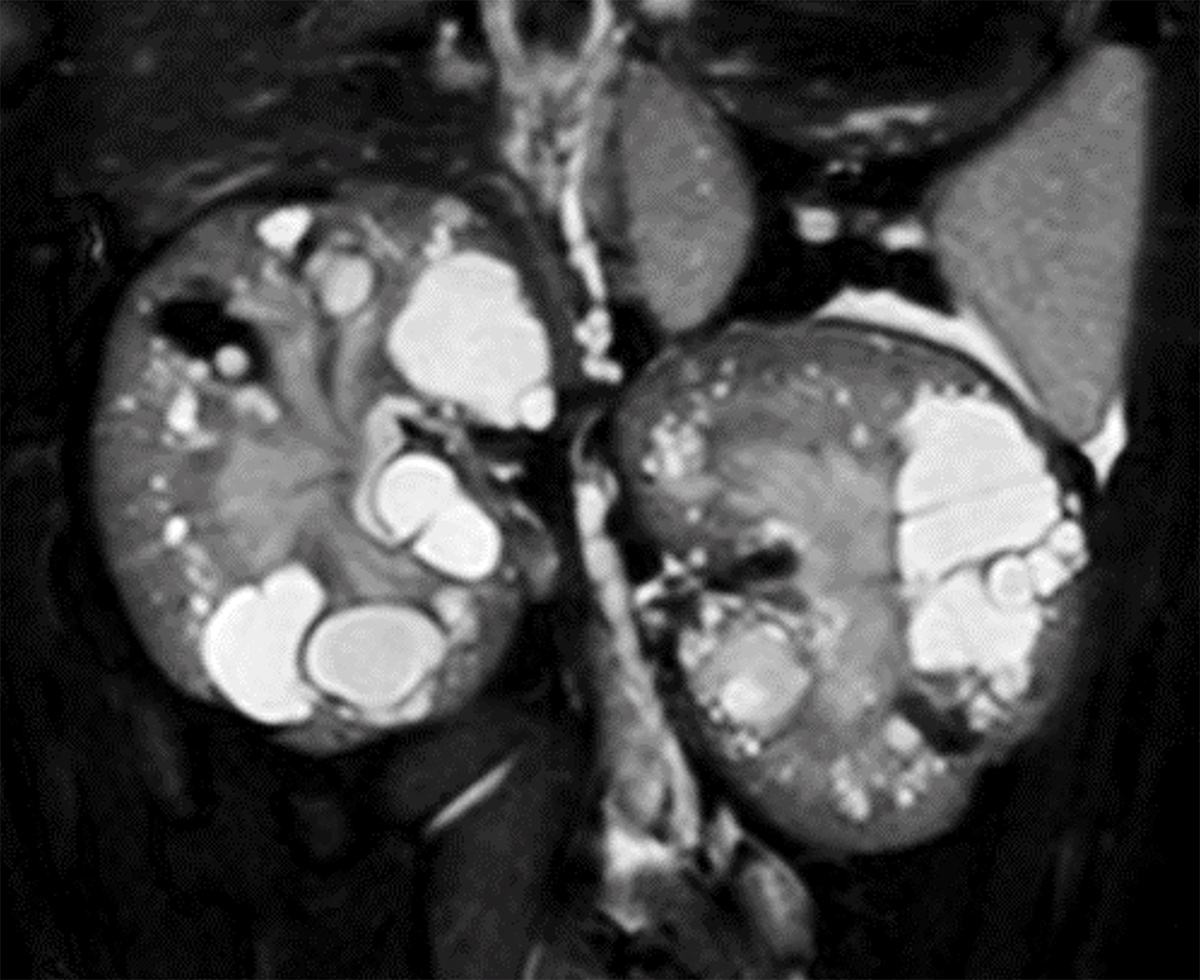

図: ネコの多発性嚢胞腎でみられるPKD1遺伝子エクソン29ナンセンス多型

多発性嚢胞腎を発症したネコの多くでPKD1遺伝子のエクソン29に”TGC”がストップコドンである”TGA”に置換するナンセンス変異(chrE3:g.42858112C>A)を認める。